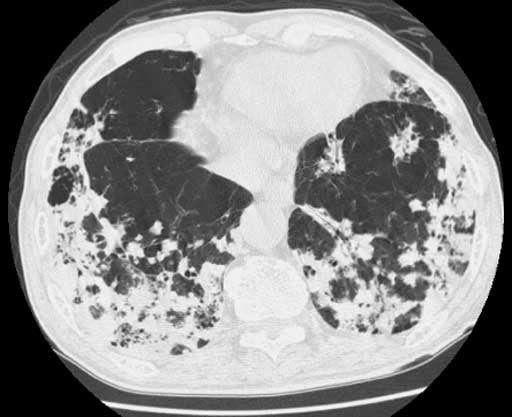

図3 Thin-slice CT 2 図4 Thin-slice CT 3

図4 Thin-slice CT 3 図5 Thin-slice CT 4